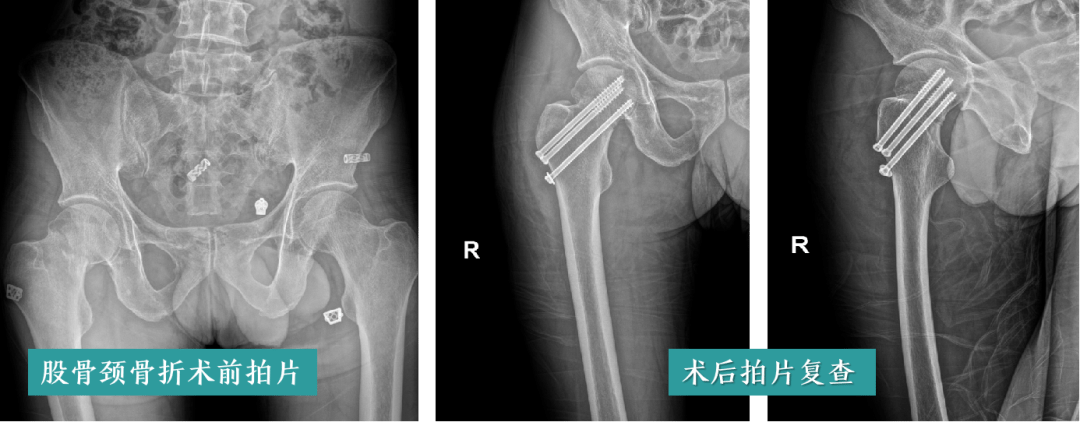

高龄老人粉碎性骨折